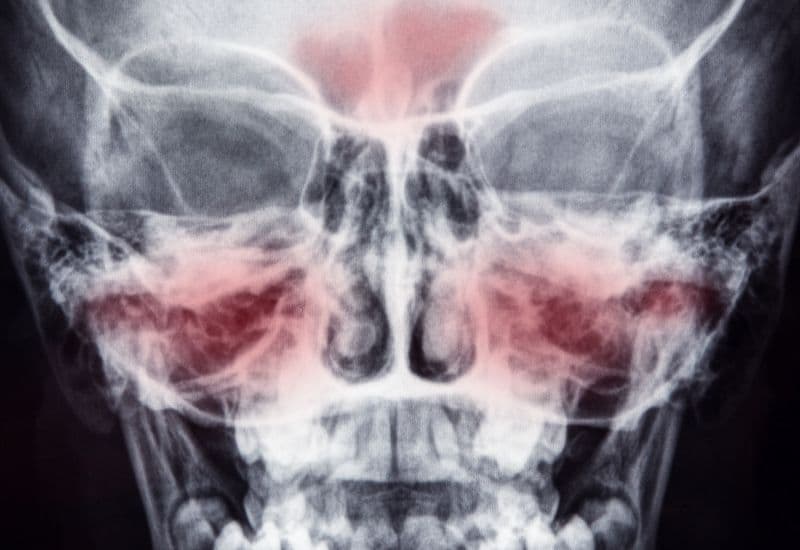

Xoang là những hốc xương rỗng, nằm trong khối xương sọ mặt, cụ thể là nằm xung quanh hốc mũi và thông với hốc mũi. Tương tự hốc mũi, các hốc xương rỗng này được bao phủ bởi một lớp niêm mạc, gọi là niêm mạc đường hô hấp. Người trưởng thành nào cũng có 5 đôi xoang, được chia thành 2 nhóm:

Viêm xoang là tình trạng niêm mạc đường hô hấp bao phủ các xoang bị viêm. Tình trạng viêm xuất hiện lần đầu thì viêm xoang được gọi là cấp tính. Khi tình trạng viêm kéo dài từ 12 tuần, viêm xoang trở thành mạn tính.